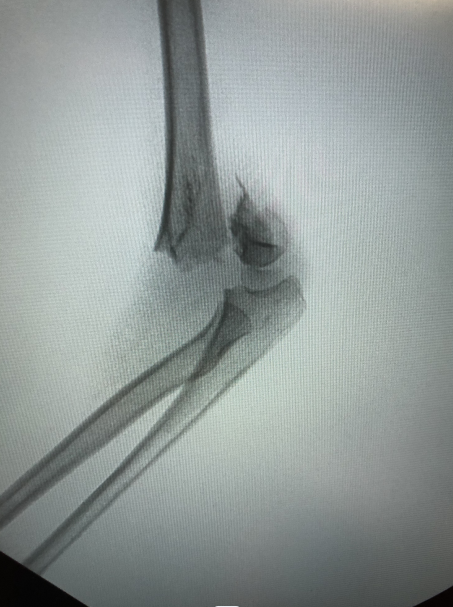

▲肱骨髁上骨折X线平片

小儿骨科康映泉副主任医师接诊后确诊是“肱骨髁上骨折”,骨折完全移位,所幸没有血管神经损伤,但仍需要手术治疗。康映泉副主任医师应用最新治疗手段,即超声引导骨折复位技术,大大降低术中辐射暴露,成功为小晨施行骨折闭合复位内固定术,术中没有伤口,针尾留置皮肤外面,待1个月后骨折愈合即可门诊拔除,无需住院或麻醉,看着无大碍的孩子,小晨爸爸悬着的心终于放下。

▲超声引导下骨折闭合复位钢针内固定及术后外观照

康映泉副主任医师介绍,自去年开始,我院小儿骨科已成功开展数十例超声引导下儿童四肢骨折微创复位、内固定,包括肱骨髁上骨折、肱骨外髁骨折、尺桡骨骨折、胫腓骨骨折等,应用超声引导技术,极大降低术中辐射暴露,特别是对于儿童患者,低辐射手术对其生长发育具有至关重要的作用。

▲超声引导下骨折闭合复位钢针内固定术